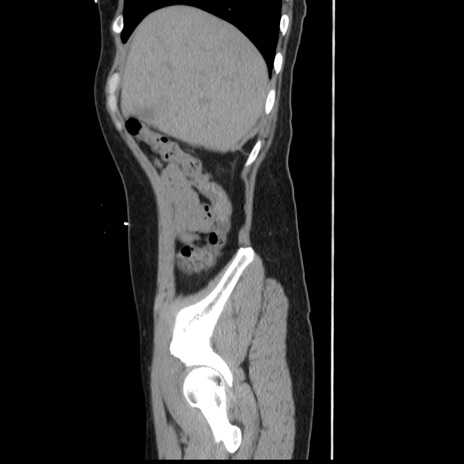

症例10(矢状断像)

【症例】 50歳代女性

【主訴】 腹痛

【現病歴】前日生レバーを食べた。今朝に排便あり。 昼前に突然発症の腹痛を生じ、当院救急外来を受診した。

【既往歴】 子宮筋腫にてで子宮全摘後

【身体所見】 意識清明、腹部:平坦、軟、下腹部やや左を中心に圧痛・反跳痛あり、筋性防御あり

【データ】WBC 7800、CRP 0.07